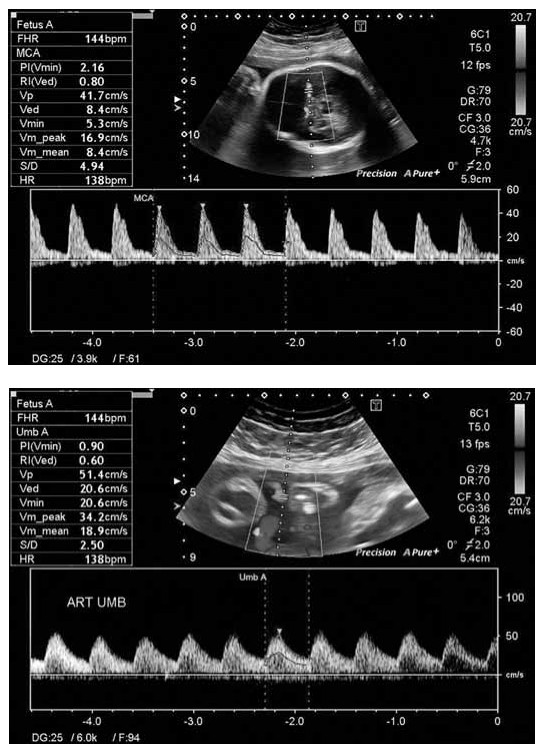

As figuras a seguir demonstram o estudo doppler de um feto de IG 32 semanas. Assinale a alternativa que traz a interpretação correta das figuras.